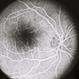

- Leber's congenital amaurosis, retinal dystrophy, genetic testing, nyctalopia

- 13-year-old female patient with severe nyctalopia, photophobia, and reduced peripheral vision. CRB1-related Leber´s Congenital Amaurosis. The ultra-widefield pseudocolor image shows attenuated arterioles and diffuse nummular pigmentation with important atrophy.